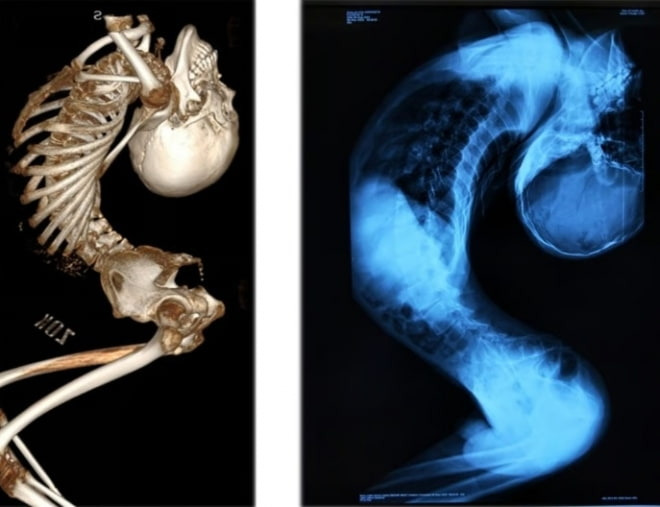

최근 중국의 한 청년이 21년간의 고통 끝에 허리를 펴는 데 성공했다는 소식이 전해졌습니다. 그는 '폴더 소년'이라는 별명으로 불리며, 그의 몸은 Z자 모양으로 휘어져 있었습니다. 이 청년은 강직성 척추염이라는 희귀 질병을 앓고 있었고, 이로 인해 그의 척추는 심각하게 변형되었습니다.

폴더 소년의 증상은 단순히 허리가 꺾이는 것에 그치지 않았습니다. 그는 일상생활에서 많은 어려움을 겪었고, 심리적으로도 큰 고통을 안고 있었습니다. 강직성 척추염은 면역체계의 이상으로 인해 발생하는 질병으로, 척추와 관절에 염증을 일으키고 결국에는 변형을 초래합니다. 정확한 원인은 아직 밝혀지지 않았지만, 유전적 요인과 환경적 요인이 복합적으로 작용하는 것으로 알려져 있습니다.